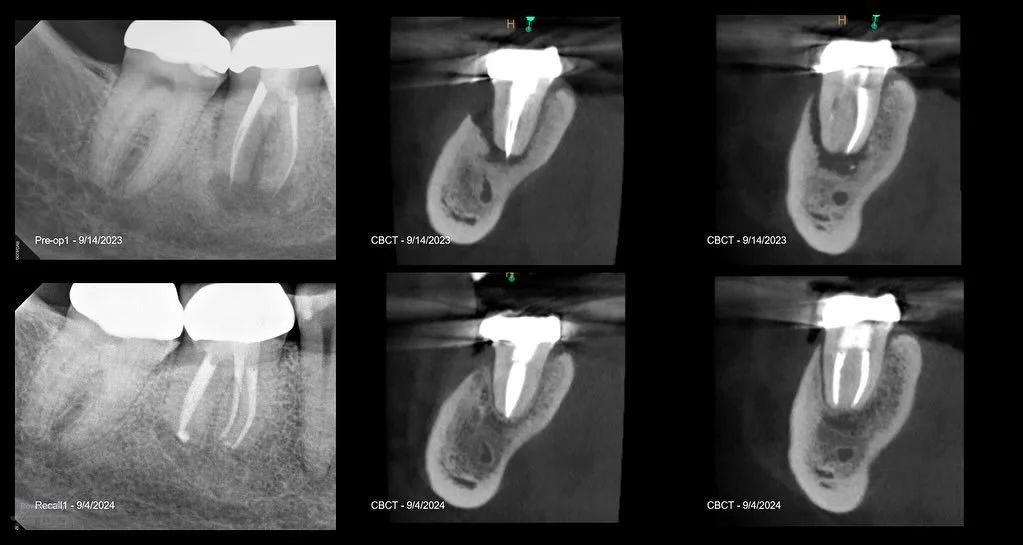

I am a board-certified endodontist with advanced specialty training and an academic interest in diagnostic reasoning, retreatment, and microsurgical endodontics. My work emphasizes CBCT-guided decision-making, interdisciplinary collaboration, and evidence-based care in complex clinical scenarios.